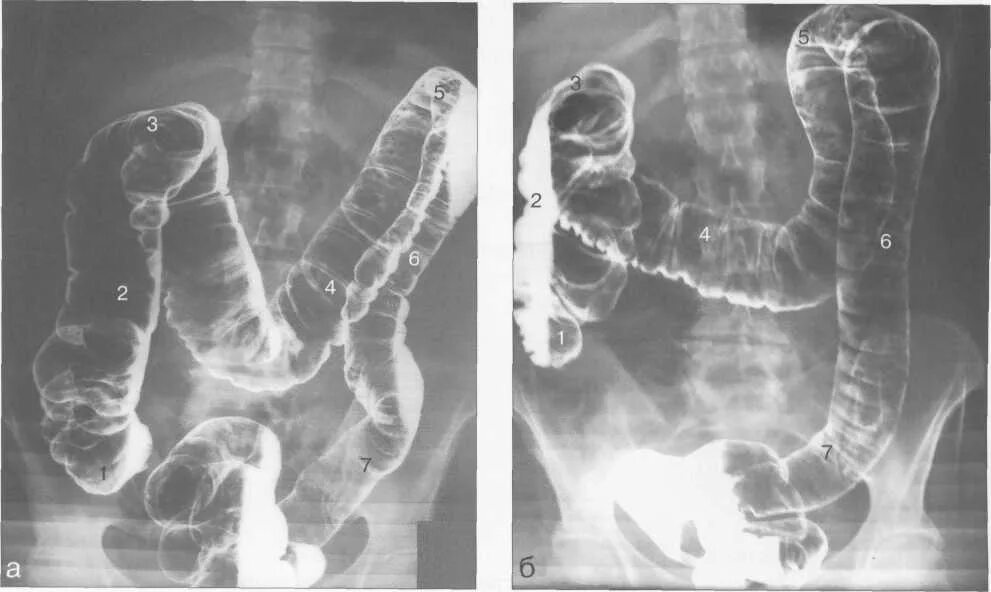

Ирригоскопия кишечника что показывает